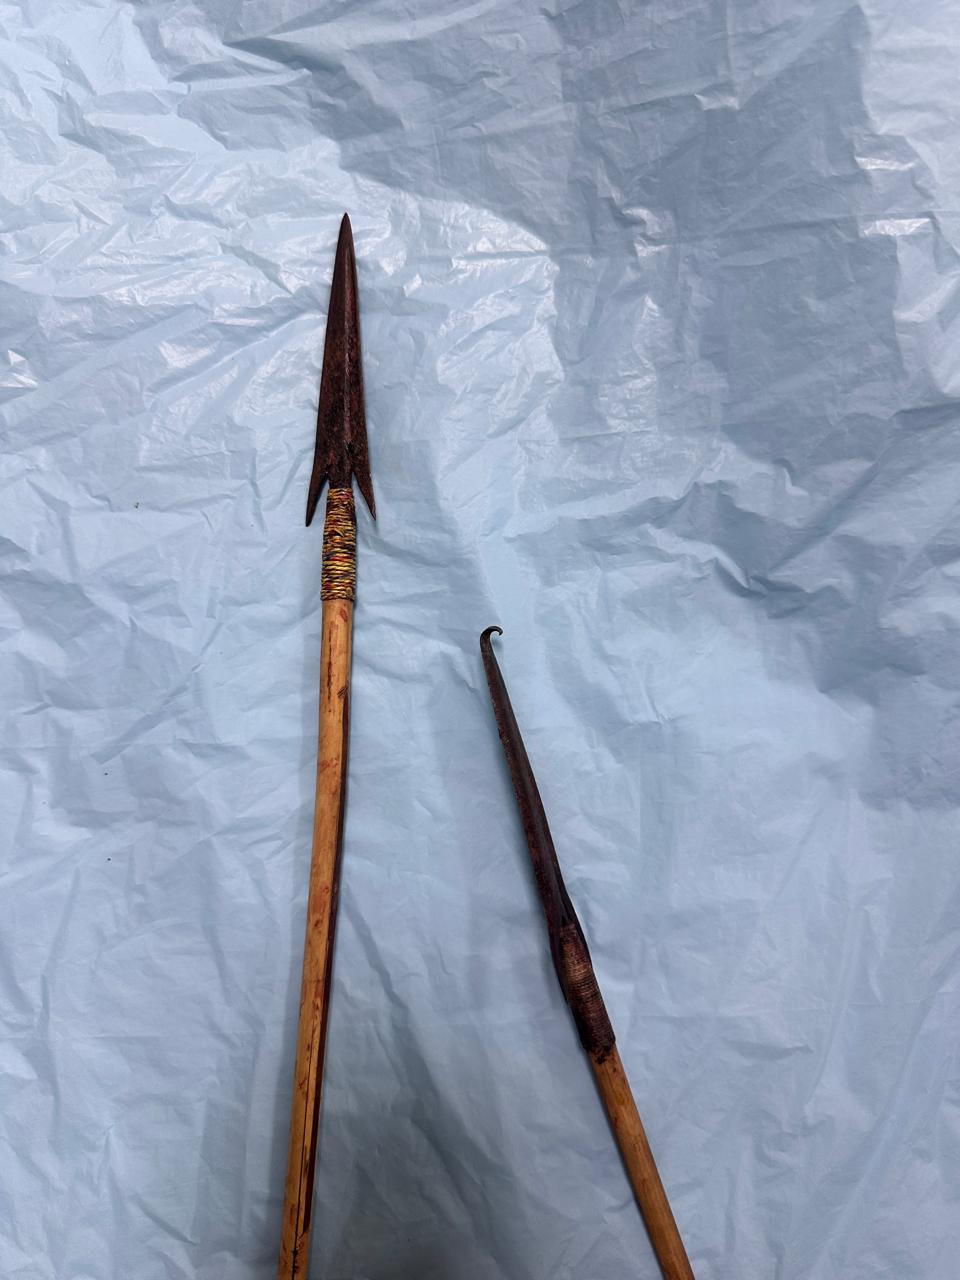

सुकमा में घरेलू विवाद के दौरान एक व्यक्ति अपने ही पुत्र द्वारा किए गए हमले में गंभीर रूप से घायल हो गया था। घटना में पीड़ित की जांघ में एक तीर धंस गया था, जबकि दूसरा तीर कलाई के पास घुसकर हाथ की महत्वपूर्ण नस (नर्व) को दबा रहा था। स्थिति अत्यंत संवेदनशील थी। समय रहते उपचार न मिलने की स्थिति में हाथ की स्थायी क्षति हो सकती थी और पीड़ित की जान को भी खतरा हो सकता था। घायल को तत्काल जगदलपुर डिमरापाल चिकित्सालय लाया गया, जहां रात्रि लगभग 2 बजे आर्थोपेडिक्स विभाग की टीम ने तत्परता से उपचार प्रारंभ किया। सहायक प्राध्यापक, आर्थोपेडिक्स विभाग डॉ. आदित्य कौशिक ने विभागाध्यक्ष डॉ. सुनीत पाल के मार्गदर्शन में जटिल शल्य प्रक्रिया को सफलतापूर्वक अंजाम दिया। चिकित्सकीय जांच में पाया गया कि यद्यपि रोगी हेमोडायनामिक रूप से अस्थिर नहीं था, फिर भी कलाई में धंसा तीर नस पर दबाव बना रहा था, जिससे स्थायी नर्व डैमेज का गंभीर खतरा उत्पन्न हो गया था। टीम द्वारा अत्यंत सावधानी और विशेषज्ञता के साथ दोनों तीरों को सुरक्षित रूप से निकाला गया। विशेष रूप से कलाई क्षेत्र में की गई सटीक प्रक्रिया के माध्यम से हाथ की नस को होने वाली संभावित क्षति को समय रहते रोक लिया गया। इस जटिल हस्तक्षेप में एनेस्थीसिया विशेषज्ञ डॉ. गुलाब सिंह काशी ने कुशलता से उपयुक्त क्षेत्रीय एनेस्थीसिया प्रदान किया, जिससे पूरी प्रक्रिया सुरक्षित और सुचारु रूप से सम्पन्न हो सकी। चिकित्सकों के अनुसार, ऐसी चोटें अत्यंत घातक सिद्ध हो सकती हैं, विशेषकर जब वे नसों के समीप हों। मध्य रात्रि में त्वरित निर्णय, अनुभवी चिकित्सकीय हाथों और समन्वित टीमवर्क के कारण यह जीवन-रक्षक उपचार संभव हो पाया। वर्तमान में रोगी की स्थिति स्थिर है और हाथ की कार्यक्षमता सुरक्षित रहने की उम्मीद जताई गई है। डॉक्टरों के टीम वर्क, अस्पताल अधीक्षक डॉ. अनुरूप साहू के कुशल नेतृत्व, समय पर चिकित्सकीय हस्तक्षेप के महत्व को और हॉस्पीटल में उपलब्ध विशेषज्ञ सेवाओं और चिकित्सकों की प्रतिबद्धता का प्रमाण प्रस्तुत करती है। डिमरापाल मेडिकल कॉलेज के अधीक्षक डॉ. अनुरूप साहू के कुशल निर्देशन में डाक्टरों की टीम बेहतर व्यवस्था के साथ मरीजों की देखरेख में जुटी है। हॉस्पीटल में साय सरकार के सुशासन की झलक साफ नजर आने लगी है।